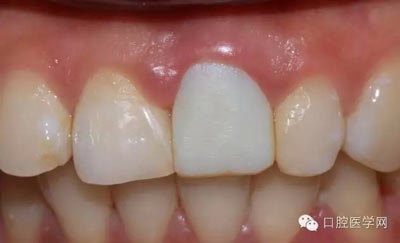

4、復(fù)診時戴臨時冠的牙齦恢復(fù)情況,恢復(fù)良好

5、3MU200樹脂粘接劑粘固全瓷冠術(shù)后照